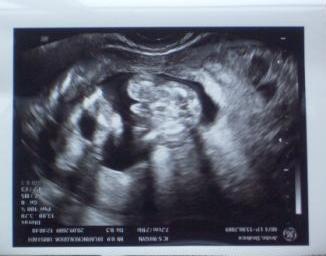

Hier das outing bildchen

Bild zu

Na, das sieht doch ziemlich eindeutig aus *ggg* Glückwunsch zum Jungen :-)

das erste ist toll, aber auf dem zweiten kann ich nix erkennen - blind? :-) LG, Jette

Hi, also das outing Bildchen wurde von unten geschallt...da hat er im Schneidersitz gehockt und man sieht also den Po, die Schenkel und den Lullumann... das erste Bild ist über den Bauch geschallt... LG Bea